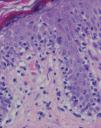

Se practicaron varias biopsias cutáneas, algunas de ellas sin alteraciones significativas. En otras se observó (figs. 4-6) una epidermis con hiperqueratosis y paraqueratosis focal, elongación de las crestas interpapilares y focos de degeneración hidrópica basal, con algún cuerpo apoptótico aislado. En dermis superficial y media existía un infiltrado linfocitario perivascular. Llamaba la atención la exocitosis de linfocitos atípicos intraepidérmicos, alguno de ellos con halo claro perinuclear y en alguna zona incluso iniciando la formación de microabscesos de Pautrier.

Fig. 6.—Exocitosis linfocitaria que muestra degeneración hidrópica basal. (Hematoxilina-eosina, ×100.)

Como ocurrió con nuestro paciente, el estudio histopatológico en los estadios iniciales de la enfermedad puede ser muy inespecífico, lo que motiva además el retraso diagnóstico. En las fases más avanzadas revela la presencia de epidermotropismo de linfocitos anómalos, que a veces constituyen microabscesos de 5,6,8,11-23. En contraste con la micosis fungoide clásica, en esta variante parece que se observa un epidermotropismo más llamativo en contraste con un infiltrado linfocitario moderado en la dermis24.